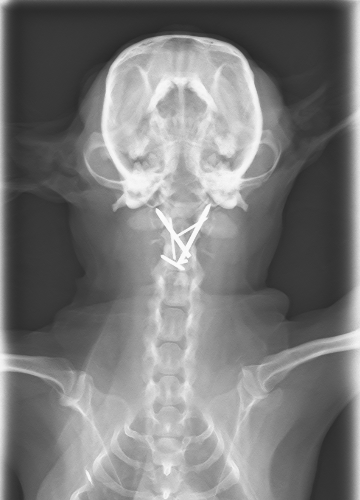

CTより軸椎歯突起の背側変移、MRIよりC1-2領域に脳脊髄液の貯留が認められた

腹側椎体固定術

before